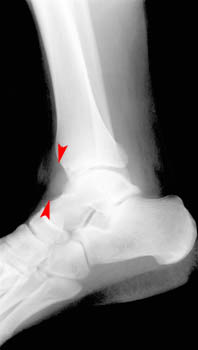

• Joint effusion is seen as a fluid density semicircle anterior to the talotibial joint on the lateral view.

Lateral view